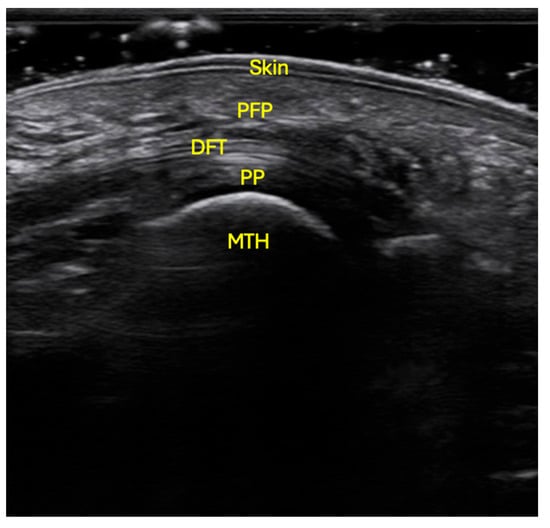

Preliminary Reference Values for Plantar Fat Pad Thickness Beneath the Metatarsal Heads and Its Relationship with Body Mass Index

Introduction and Objectives: The thickness of the plantar fat pad (PFP) beneath the metatarsal heads may play a protective role in preventing forefoot disorders such as metatarsalgia. However, reference values for plantar adipose tissue thickness in this region among healthy individuals are currently unavailable. Therefore, the aim of this study was to determine, by means of ultrasound imaging, the thickness of the PFP beneath the five metatarsal heads and to analyze its possible relationship with body mass index (BMI). Materials and Methods: Thirty-five young adults (17 males and 18 females) with neutral feet, free from deformities or pain, participated in the study. Using a VINNO E35 ultrasound device, the thickness of the PFP beneath each of the five metatarsal heads was quantified. A linear transducer was positioned longitudinally along the axis of each metatarsal. The distance between the dermis and the flexor tendon was measured from the second to the fifth metatarsal heads, and from the fibular sesamoid for the first metatarsal head. Results: The central forefoot showed the greatest PFP thickness (2nd metatarsal head, 7.1 ± 0.9 mm; 3rd metatarsal head, 6.9 ± 0.9 mm). No significant differences in PFP thickness were found between sexes. However, a positive correlation was observed between BMI and PFP thickness at the fourth metatarsal head (r = 0.358, p = 0.035). Conclusions: The study demonstrated greater PFP thickness beneath the second and third metatarsal heads, with no significant sex-related differences. These findings indicate a consistent anatomical pattern independent of sex in young, healthy individuals. Moreover, a moderate influence of BMI was identified at the fourth metatarsal head, which could represent a potential protective mechanism against forefoot overload. Full article